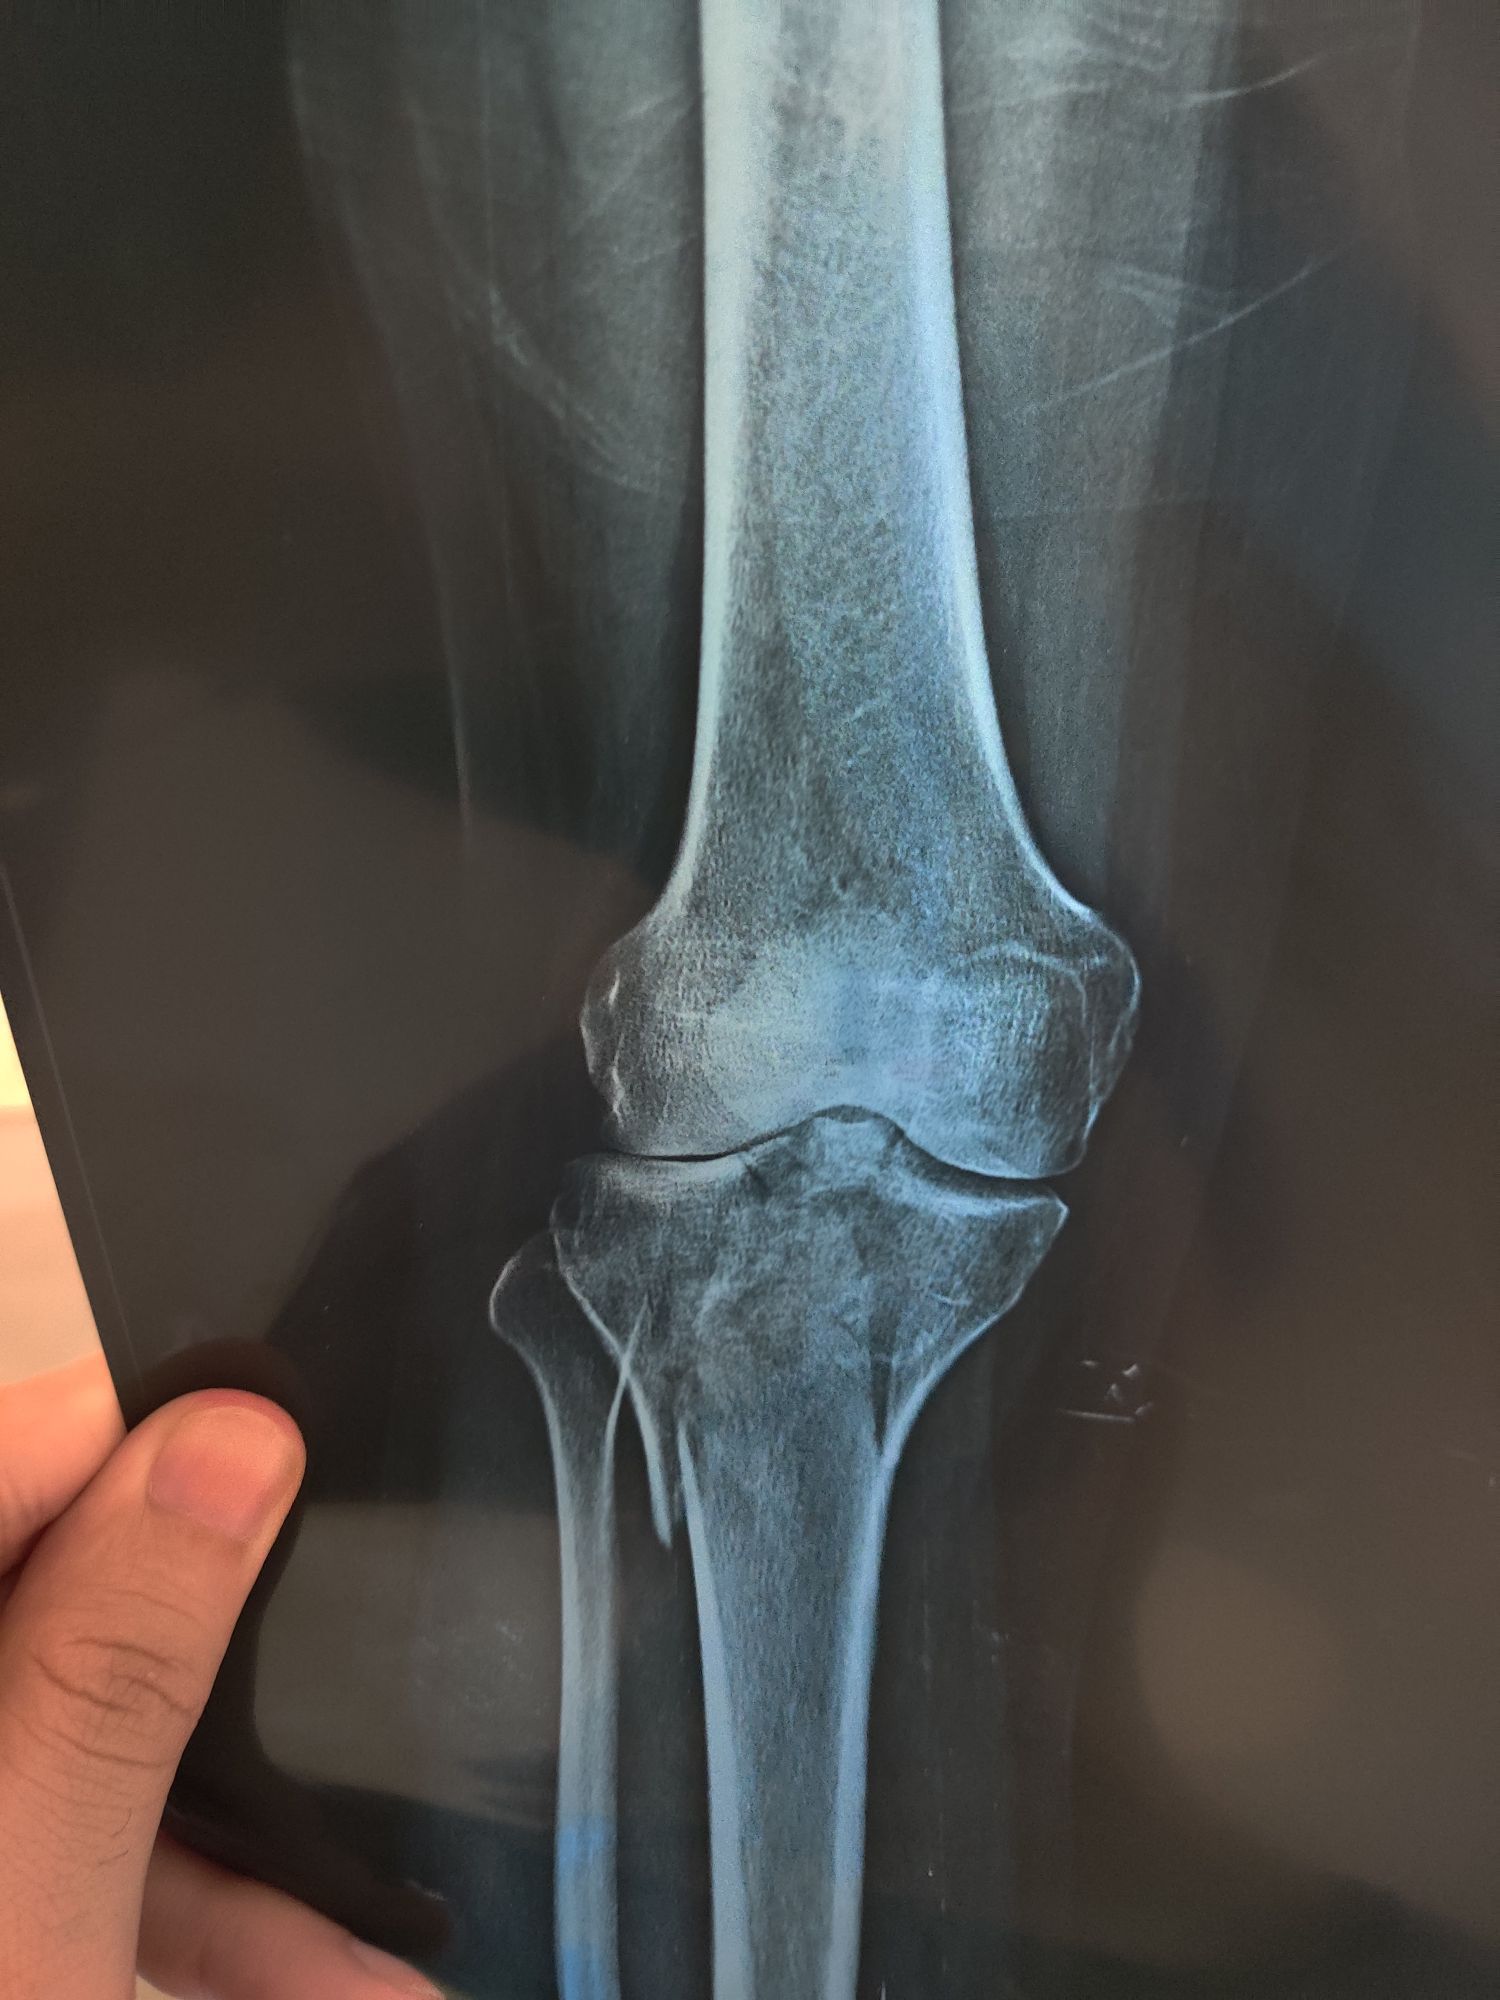

Tibia Fx

Schatzker V